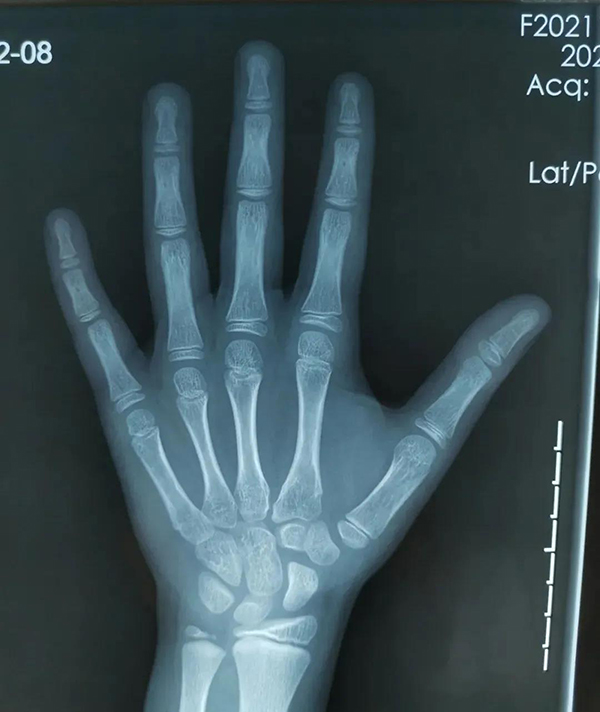

評(píng)估骨齡最常見的方法是拍攝左手(包含全掌和腕部)X 光正位片。具有操作簡便、檢查時(shí)間短、檢查費(fèi)用低的特點(diǎn),故目前仍以 X 線平片作為骨齡評(píng)估的主要手段。臨床上評(píng)估骨齡以左手及腕關(guān)節(jié)作為最常見的評(píng)測(cè)部位,通過觀察相應(yīng)的腕部骨化中心、左手掌指骨骨化中心的個(gè)數(shù)、形態(tài)來評(píng)估骨齡。因此,獲得用于骨齡評(píng)估的左手及腕關(guān)節(jié)的圖像是骨齡評(píng)估的第一步。骨齡圖像的關(guān)鍵骨化中心包括遠(yuǎn)端橈骨、遠(yuǎn)端尺骨、腕骨。

徐州市婦幼保健院為準(zhǔn)確測(cè)算骨齡,由放射科專業(yè)人員攝片獲取標(biāo)準(zhǔn)X線片圖像,通過準(zhǔn)確定位,清晰拍攝,保證手腕骨的影像質(zhì)量。另外,醫(yī)院還引進(jìn)了先進(jìn)的骨齡影像智能檢測(cè)系統(tǒng),該系統(tǒng)依據(jù)臨床常用指標(biāo)(包括兒童身高體重,父母身高等參數(shù)),可自動(dòng)生成詳細(xì)完善的診斷報(bào)告,包含骨齡評(píng)價(jià)、身高評(píng)價(jià)、發(fā)育評(píng)價(jià)、身高預(yù)測(cè)等指標(biāo)。隨后,結(jié)合專業(yè)骨齡讀片醫(yī)生人工讀片,既能夠保證結(jié)果的精準(zhǔn)度,同時(shí)也能夠提高讀片的效率。